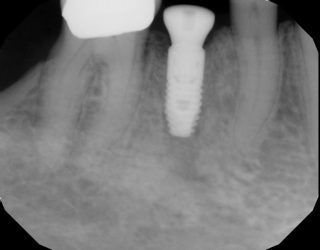

Hey guys, I have a restorative question. This patient is from Argentina and has a TQu4tro Tip implant, #12. (also manufactured in Argentina). When the patient presented to my practice 1 year ago it had a temporary crown which broke. I removed it an placed an Implant club healing abutment. I reached out to the implant manufacturer to ask…